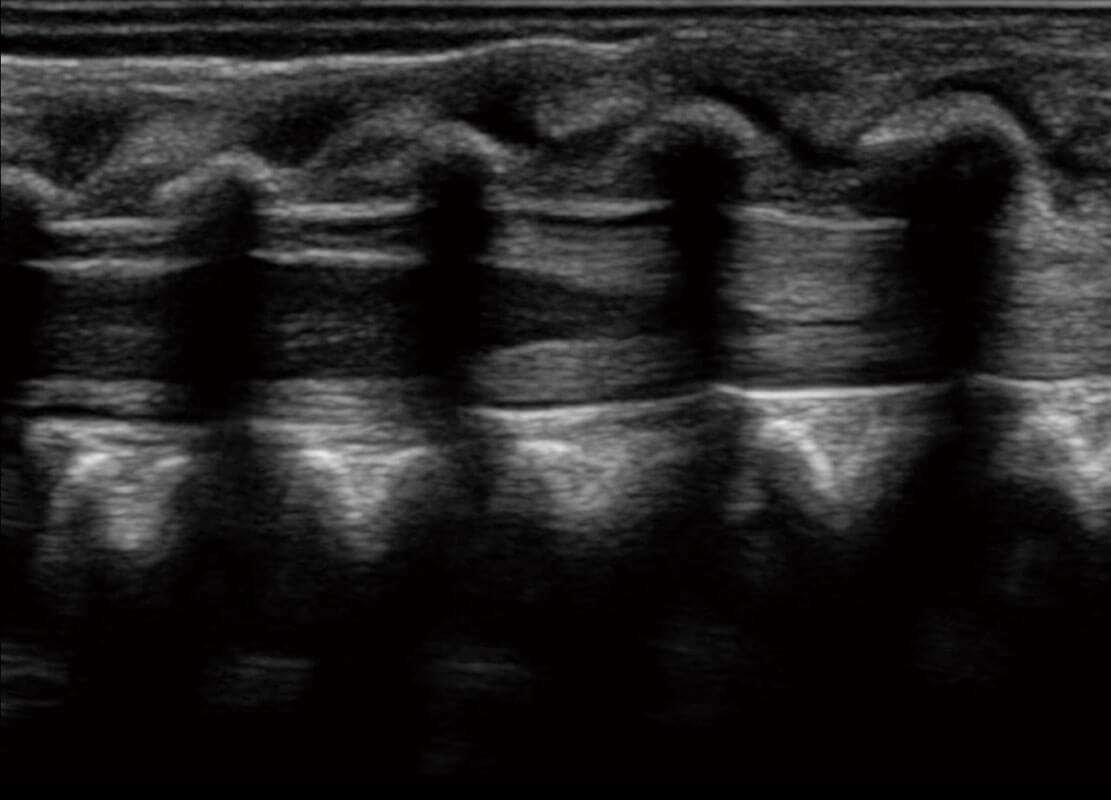

P60在胎儿早孕期超声筛查中为您带来优异的图像质量。

早孕-胎心